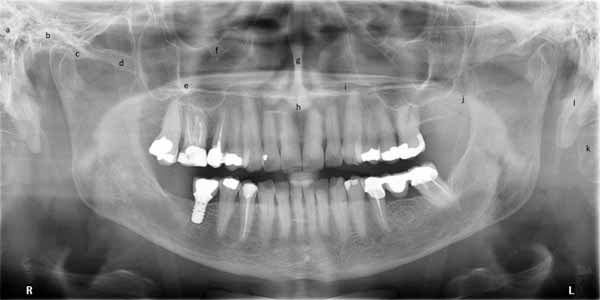

顎と頭蓋骨の中にはいくつかの空洞があり、パノラマ画像で確認することができます。口腔内画像で解剖学的構造を検討した際に、これらのいくつかについてすでに言及しました。これらには、鼻腔、上顎洞、切歯孔、下顎管が含まれます。

パノラマX線ではより広い範囲を観察できるため、歯槽頂の外側にある他の空洞も確認できます。これらには、眼窩、外耳道、翼口蓋窩、中頭蓋窩が含まれます。(画像26参照)

(a)上顎洞(下方および後方境界)

(b)鼻腔

(c)翼口蓋窩

(d)中頭蓋窩

(e)下顎管

(f)切歯孔

(g)外耳道

(h)眼窩

パノラマ画像の両側の端には、頸椎の輪郭が見えます。頭蓋底の一部と、乳様突起と茎状突起という 2 つの骨の突起も見ることができます。パノラマ画像では、舌骨が二重に撮影され、下顎の基部のすぐ下で両側から確認できます。さらに、顎関節、上顎と下顎の全体、中顔面の一部を構成する構造を見ることができます。(画像27aと27bを参照)

(a)乳様突起

(b)顎関節

(c)関節結節

(d)頬骨

(e)歯槽骨

(f)眼窩下管

(g)鼻中隔

(h)前鼻棘

(i)硬口蓋

(j)管

(k)頸椎

(l)茎状突起

(a)顆頭

(b)切歯

(c)冠状突起

(d)後枝制限

(e)下顎角

(f)顎下窩

(g)基底骨

(h)背骨

(i)オトガイ孔

(j)舌骨